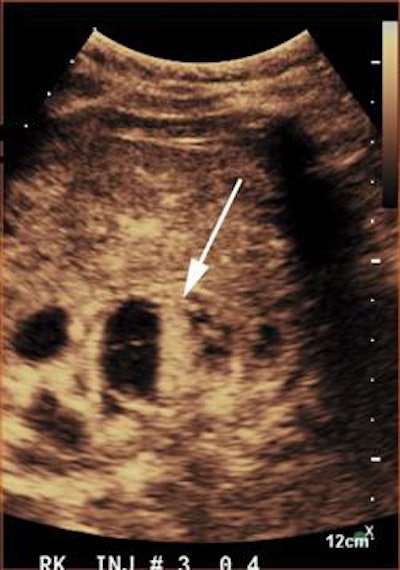

After first receiving conventional grayscale ultrasound to localize the renal lesion and determine the best plane for the contrast study, the CEUS exams were performed using a low mechanical index on either an iU22 (Philips Healthcare) or Epiq 7 (Philips) ultrasound scanner equipped with a C5-2 or C9-2 transducer. Once they had completed a safety questionnaire to assess for any potential contraindication to receiving microbubble contrast agents, the patients received intravenous bolus injections of the Definity (Lantheus Medical Imaging) or SonoVue (Bracco Diagnostics) ultrasound contrast agents. Most patients received one to three doses of contrast material, depending on if there were multiple lesions or if additional imaging was necessary, according to the researchers.

The radiologists were able to classify 90 (95.7%) of the 94 previously indeterminate renal lesions successfully. The remaining four indeterminate lesions included one case in the setting of acute hemorrhage and three with technical limitations due to a large body habitus and a small lesion diameter.